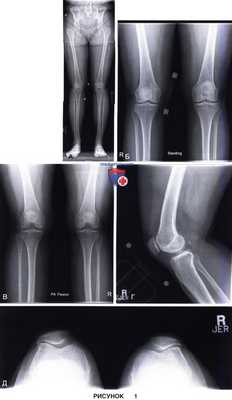

д) Рентгенологическое обследование включает полноразмерные рентгенограммы конечности целиком, рентгенограммы коленного сустава стоя в переднезадней проекции, в заднепередней проекции при сгибании, боковой проекции и проекции Merchant (рис. 1)

е) Рентгенограммы в боковой проекции должны быть высокого качества и обеспечивать возможность диагностики дисплазии блока (описанные DeJour симптом пересечения, надблоковая шпора и двойной контур) (рис. 2)